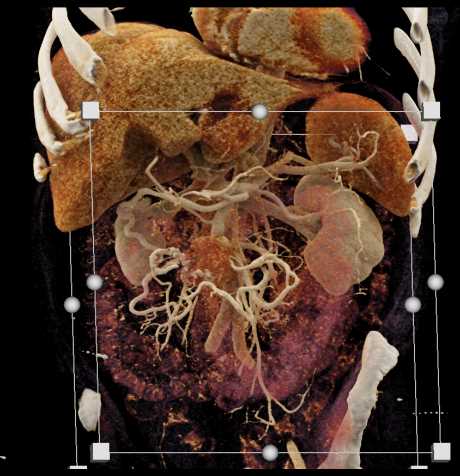

Carcinoid Tumor with Desmoplastic Reaction